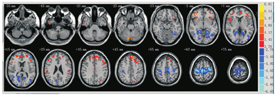

两独立样本t检验分析发现BECTS患儿与健康儿童之间存在显著差异(蓝色代表ReHo值显著降低区域,提示脑功能活性减弱;而红色代表ReHo值显著增高区域,提示脑功能活性增强),结果见图1,表1、表2。

注:BECTS:伴中央颞区棘波的儿童良性癫痫;HC:健康对照;红色表示BECTS组ReHo值较健康对照组增加;蓝色表示BECTS组ReHo值较健康对照组降低 BECTS:benign epilepsy in children with central-temporal spikes;HC:healthy control;red indicates an increased ReHo value,BECTS>control group;blue indicates a decreased ReHo value,BECTS<control group

如图1所示,根据不同脑区颜色的不同可直观显示BECTS患儿脑功能在某些特定区域出现显著的变化。与健康对照组比较,BECTS组患儿出现默认模式网络(DMN)区域ReHo值显著降低,其区域包括双侧楔前叶、楔叶以及左侧扣带回皮质,差异有统计学意义(P<0.001),见表1。BECTS患儿右侧角回、颞下回、颞中回和左侧颞上回、额中回、中央前回、辅助运动区ReHo值显著下降。与健康对照组儿童比较,BECTS组患儿双侧小脑、右侧颞上回、岛盖、缘上回、额中回和左侧顶叶、顶上小叶、下额叶皮质、额上回、前扣带回、额极区、下前扣带皮质ReHo值显著增高,差异均有统计学意义(均P<0.001),见表2。